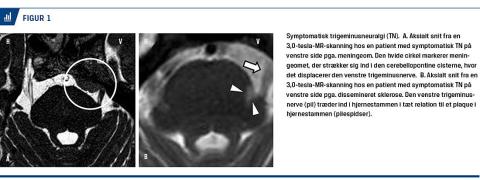

TN inddeles i en klassisk form uden intrakranial patologi og en symptomatisk form, som er sekundær til for eksempel en tumor i den cerebellopontine vinkel eller dissemineret sklerose (Figur 1).

TN er meget sjældent bilateral og er da ofte relateret

til dissemineret sklerose [7, 12]. I 70% af tilfældene involverer smerten anden og/eller tredje trigeminusgren [7].